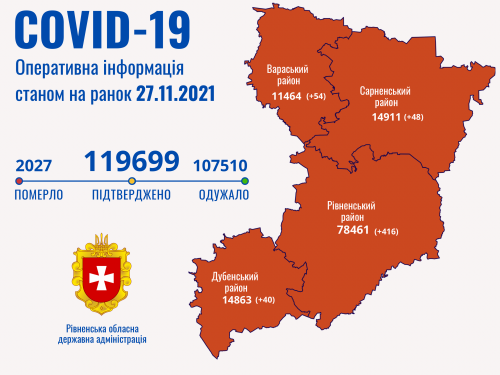

Пів тисячі - у важкому стані, 9 жителів Рівненщини померли за добу від коронавірусу